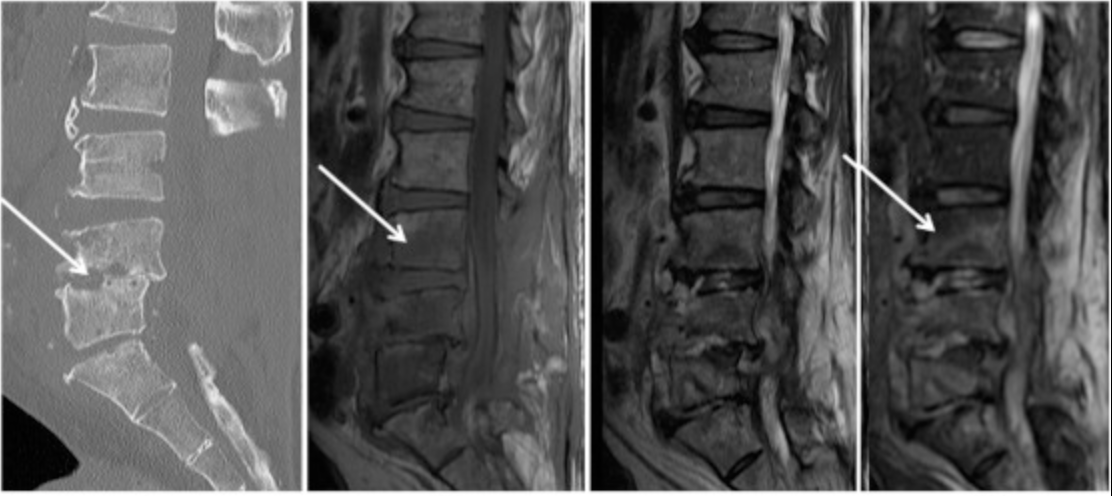

Diagnosis

Accurate diagnosis is crucial and may include:

- Blood tests (ESR, CRP, blood cultures)

- MRI spine (gold standard for early detection)

- CT scan for bone involvement

- Biopsy or aspiration to identify the causative organism